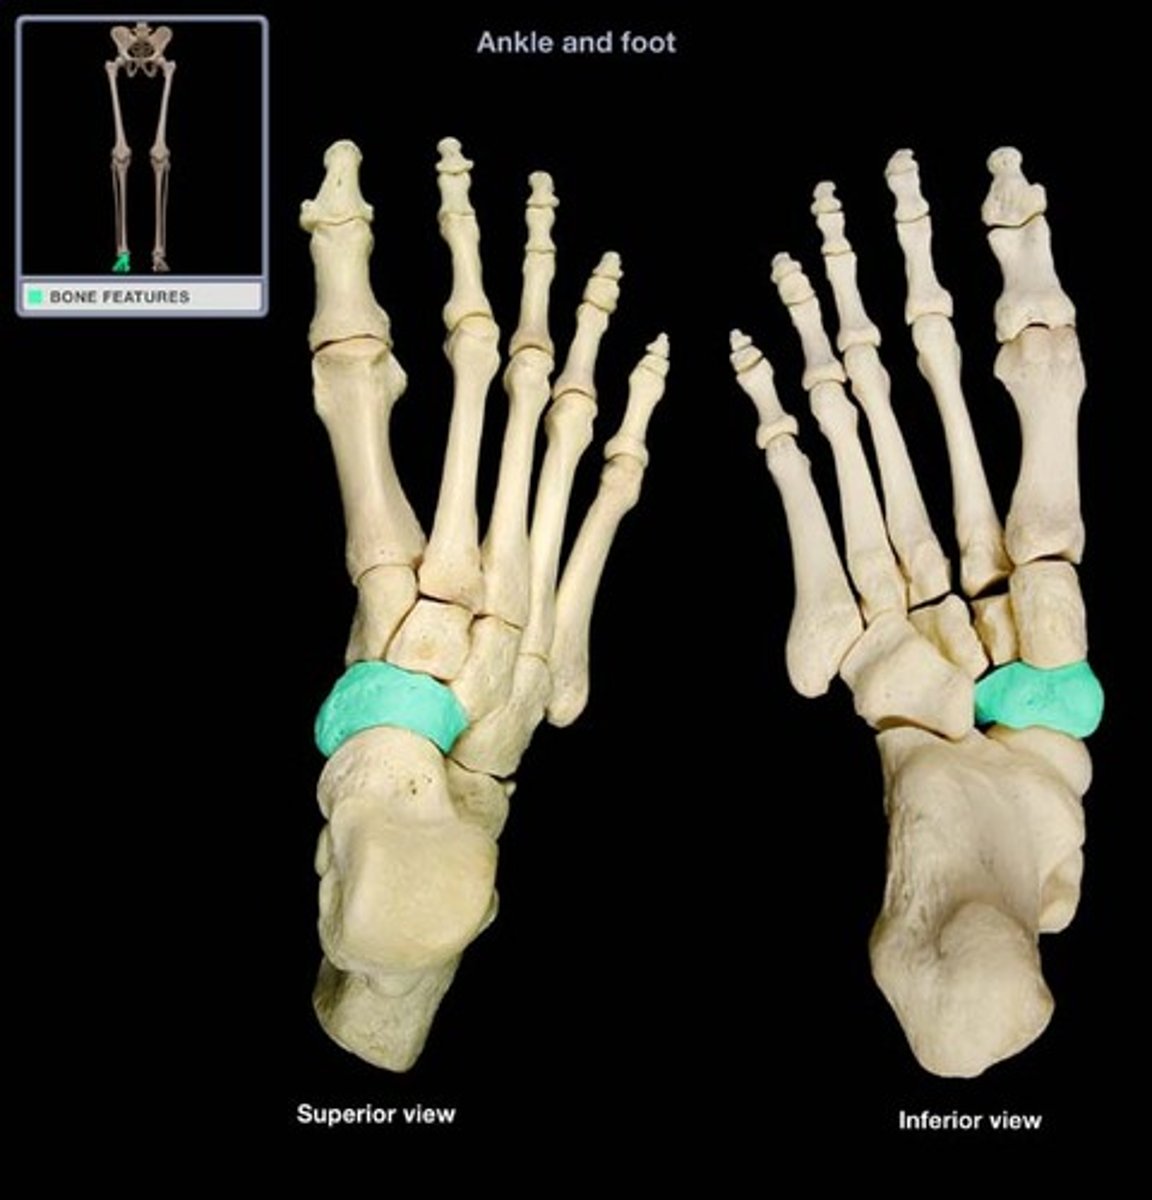

phalanges

metatarsals

tarsals

transverse arch

longitudinal arch